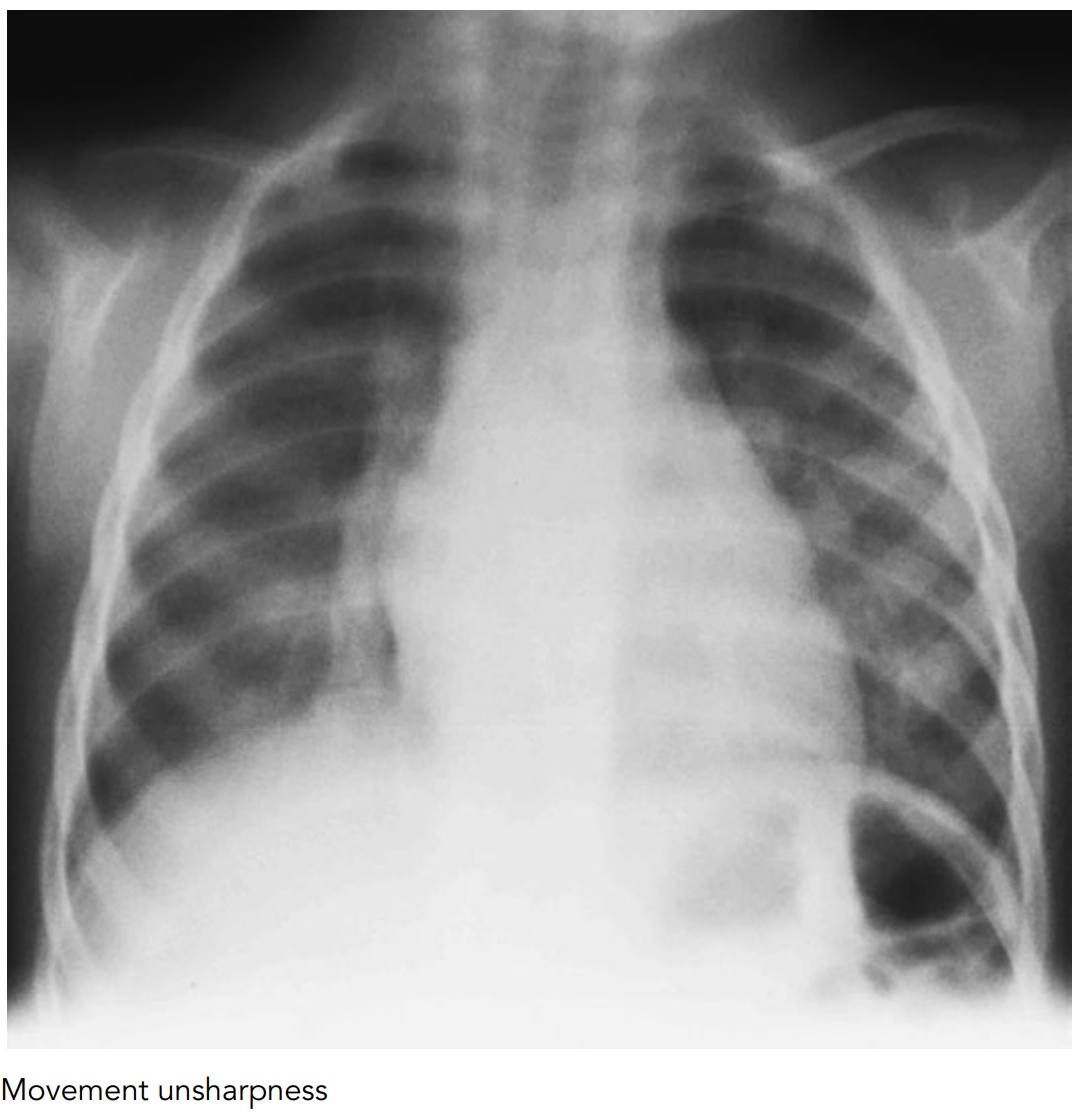

Image Parallax X Ray Parallax refers to the apparent movement of an object based on the position of the beam. The horizontal parallax involves taking of two radiographs at different horizontal angles and with the same vertical angulation. In the upper diagram, the earth in its orbit sweeps the parallax angle subtended on the sun. Due to parallax the more distant. Increasing sod similarly. Parallax X Ray.